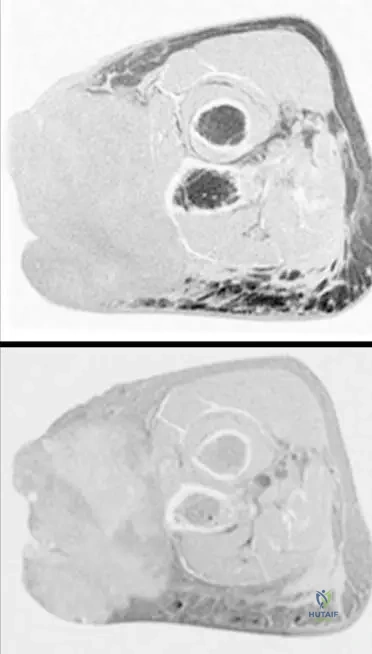

A 52-year-old male presents with a firm mass in his proximal forearm. An MRI is performed to evaluate the extent and characteristics of the lesion.

Correct Answer: A

Rationale: The clinical context for Fig. 9.15 states: "Axial T1(a) and T2-weighted image with gadolinium and fat saturation (b) showing a heterogeneous soft tissue sarcoma in the proximal forearm that is predominantly in the subcutaneous tissues abutting the adjacent myofascial plane." Main Distractor: B) Entirely within the deep muscular compartment. The image context explicitly states the lesion is "predominantly in the subcutaneous tissues," which contradicts a purely deep muscular location.

A 60-year-old female presents with a growing mass in her proximal forearm. MRI images are obtained to characterize the lesion.

Rationale: The clinical context for Fig. 9.15 describes the lesion as a "heterogeneous soft tissue sarcoma." Heterogeneity is a common feature of sarcomas due to varying cellularity, necrosis, and hemorrhage. Main Distractor: B) Uniform signal intensity throughout the mass. This is incorrect, as the text explicitly describes the sarcoma in this image as "heterogeneous."